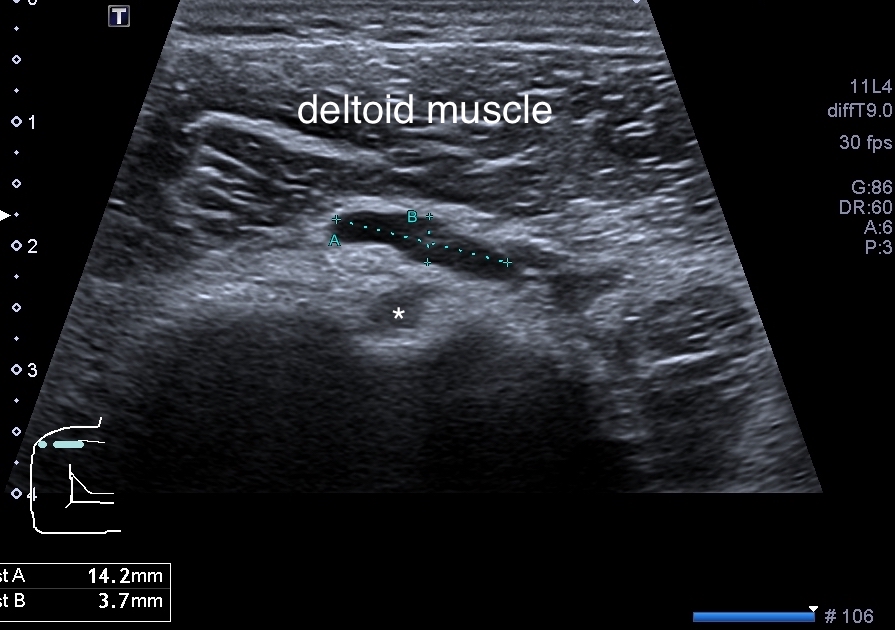

個案42歲男性,右肩部疼痛,無法上抬手臂。無外傷、無發燒,外觀無明顯紅腫。超音波呈現為SASD bursitis(subacromial-subdeltoid bursitis, 肩峰下-三角肌下滑囊炎) (圖片5、影片6),經超音波導引抽吸後疼痛顯著改善(影片7)。

圖片542歲男性,右肩疼痛。超音波標示為SASD bursitis (subacromial-subdeltoid bursitis, 肩峰下-三角肌下滑囊炎)。

星號標註為二頭肌長頭肌腱(LHBT - long head of biceps tendon)